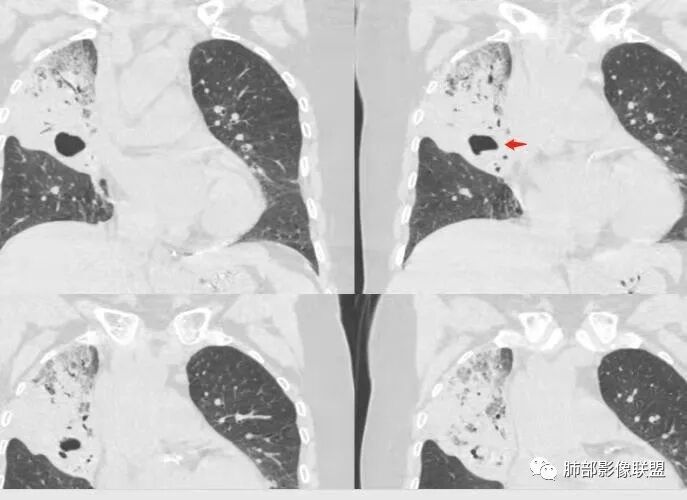

胸CT:右肺上叶实变内可见支气管充气征,近端支气管狭窄,远端扩张,周围可见毛玻璃影,右肺中叶支气管闭塞,并可见气道壁钙化,右肺中叶体积缩小,实变内可见空洞,并可见气液平面,空洞周围可见毛玻璃样影,右肺下叶支气管开口狭窄,右肺门淋巴结肿大。纵隔窗可见病灶与壁层胸膜间隙增宽,考虑良性病变-----感染性病变------TB?

1.右上肺大片状影,周围有磨玻璃影,支气管截断征、枯枝征、远端支气管充气征,可见多个大小不等囊泡(支气管阻塞活瓣作用形成),病灶有少许收缩力感,叶间裂被稍牵拉内移;

老年女性,慢性病程,咳嗽伴白色粘液痰,无发热腹痛,糖尿病,白细胞及C反应蛋白不高,血沉快,铁蛋白高。胸部CT,右肺上叶大片状实变伴磨玻璃密度影,边界不清,边缘局部膨隆,叶裂弧形下坠,实变影宽基底与胸膜相贴;右肺下叶前基底段见类似病灶;右肺中叶不张并空洞形成,空洞内见气液平面;综合考虑右肺上叶及下叶肺炎型肺癌,右肺中叶结核。

白色粘液痰,枯树枝,支气管僵直,有空洞,磨玻璃,叶间裂膨隆、下坠,吴婧老师的肺炎型粘液性腺癌十大特点中占了好多条,所以考虑粘液腺癌,就差增强看看强化如何,血管如何了

患者老年女性,亚急性起病,胸部CT:右肺上叶大片实变,可内见坏死性空洞,可见mGGO,GGO边缘清晰,局部彭隆,内见支气管充气征,可惜没增强,粘液腺癌要考虑,但病灶明显是内朝外不支持,综合考虑结核,建议查痰找抗酸杆菌、气管镜

实变区像支气管爬行征?空洞区也有钙化和边界清楚模玻璃影

3.熊老师告诉我们:肺结核可以有磨玻璃,这个我以前一直不知道,右肺门淋巴结有钙化,病灶内纵膈窗隐约细细点状钙化,所以结核磨玻璃可以,

这些层面的支气管我觉得像结核的狭窄后扩张,